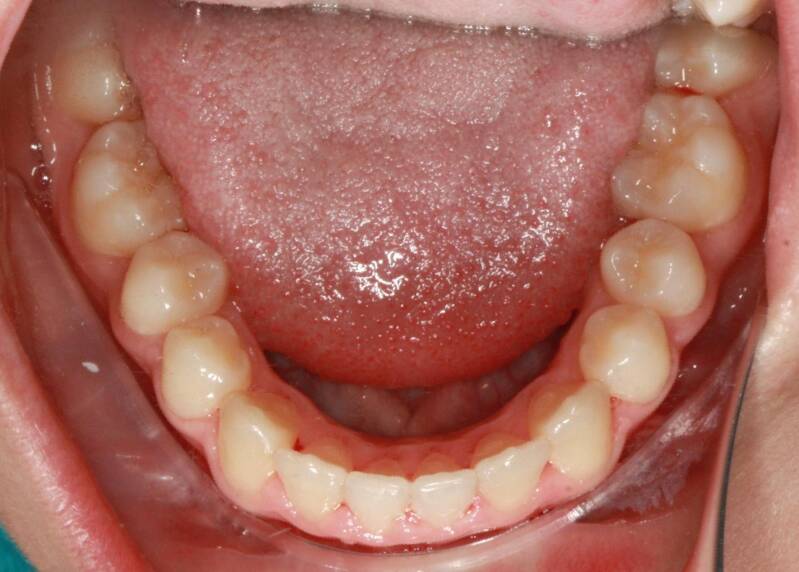

FOTO INIZIALI PRE TRATTAMENTO ORTODONTICO

PRIMA CLASSE CON AFFOLLAMENTO GRAVE SUPERIORE A SINISTRA CON PERDITA PRECOCE DEL SECONDO MOLARE INFERIORE SINISTRO

Abbiamo appena portato a termine questo caso che presentava in arcata superiore il primo premolare di sinistra completamente fuori arcata sovrapposto al secondo premolare ed il canino ruotato.